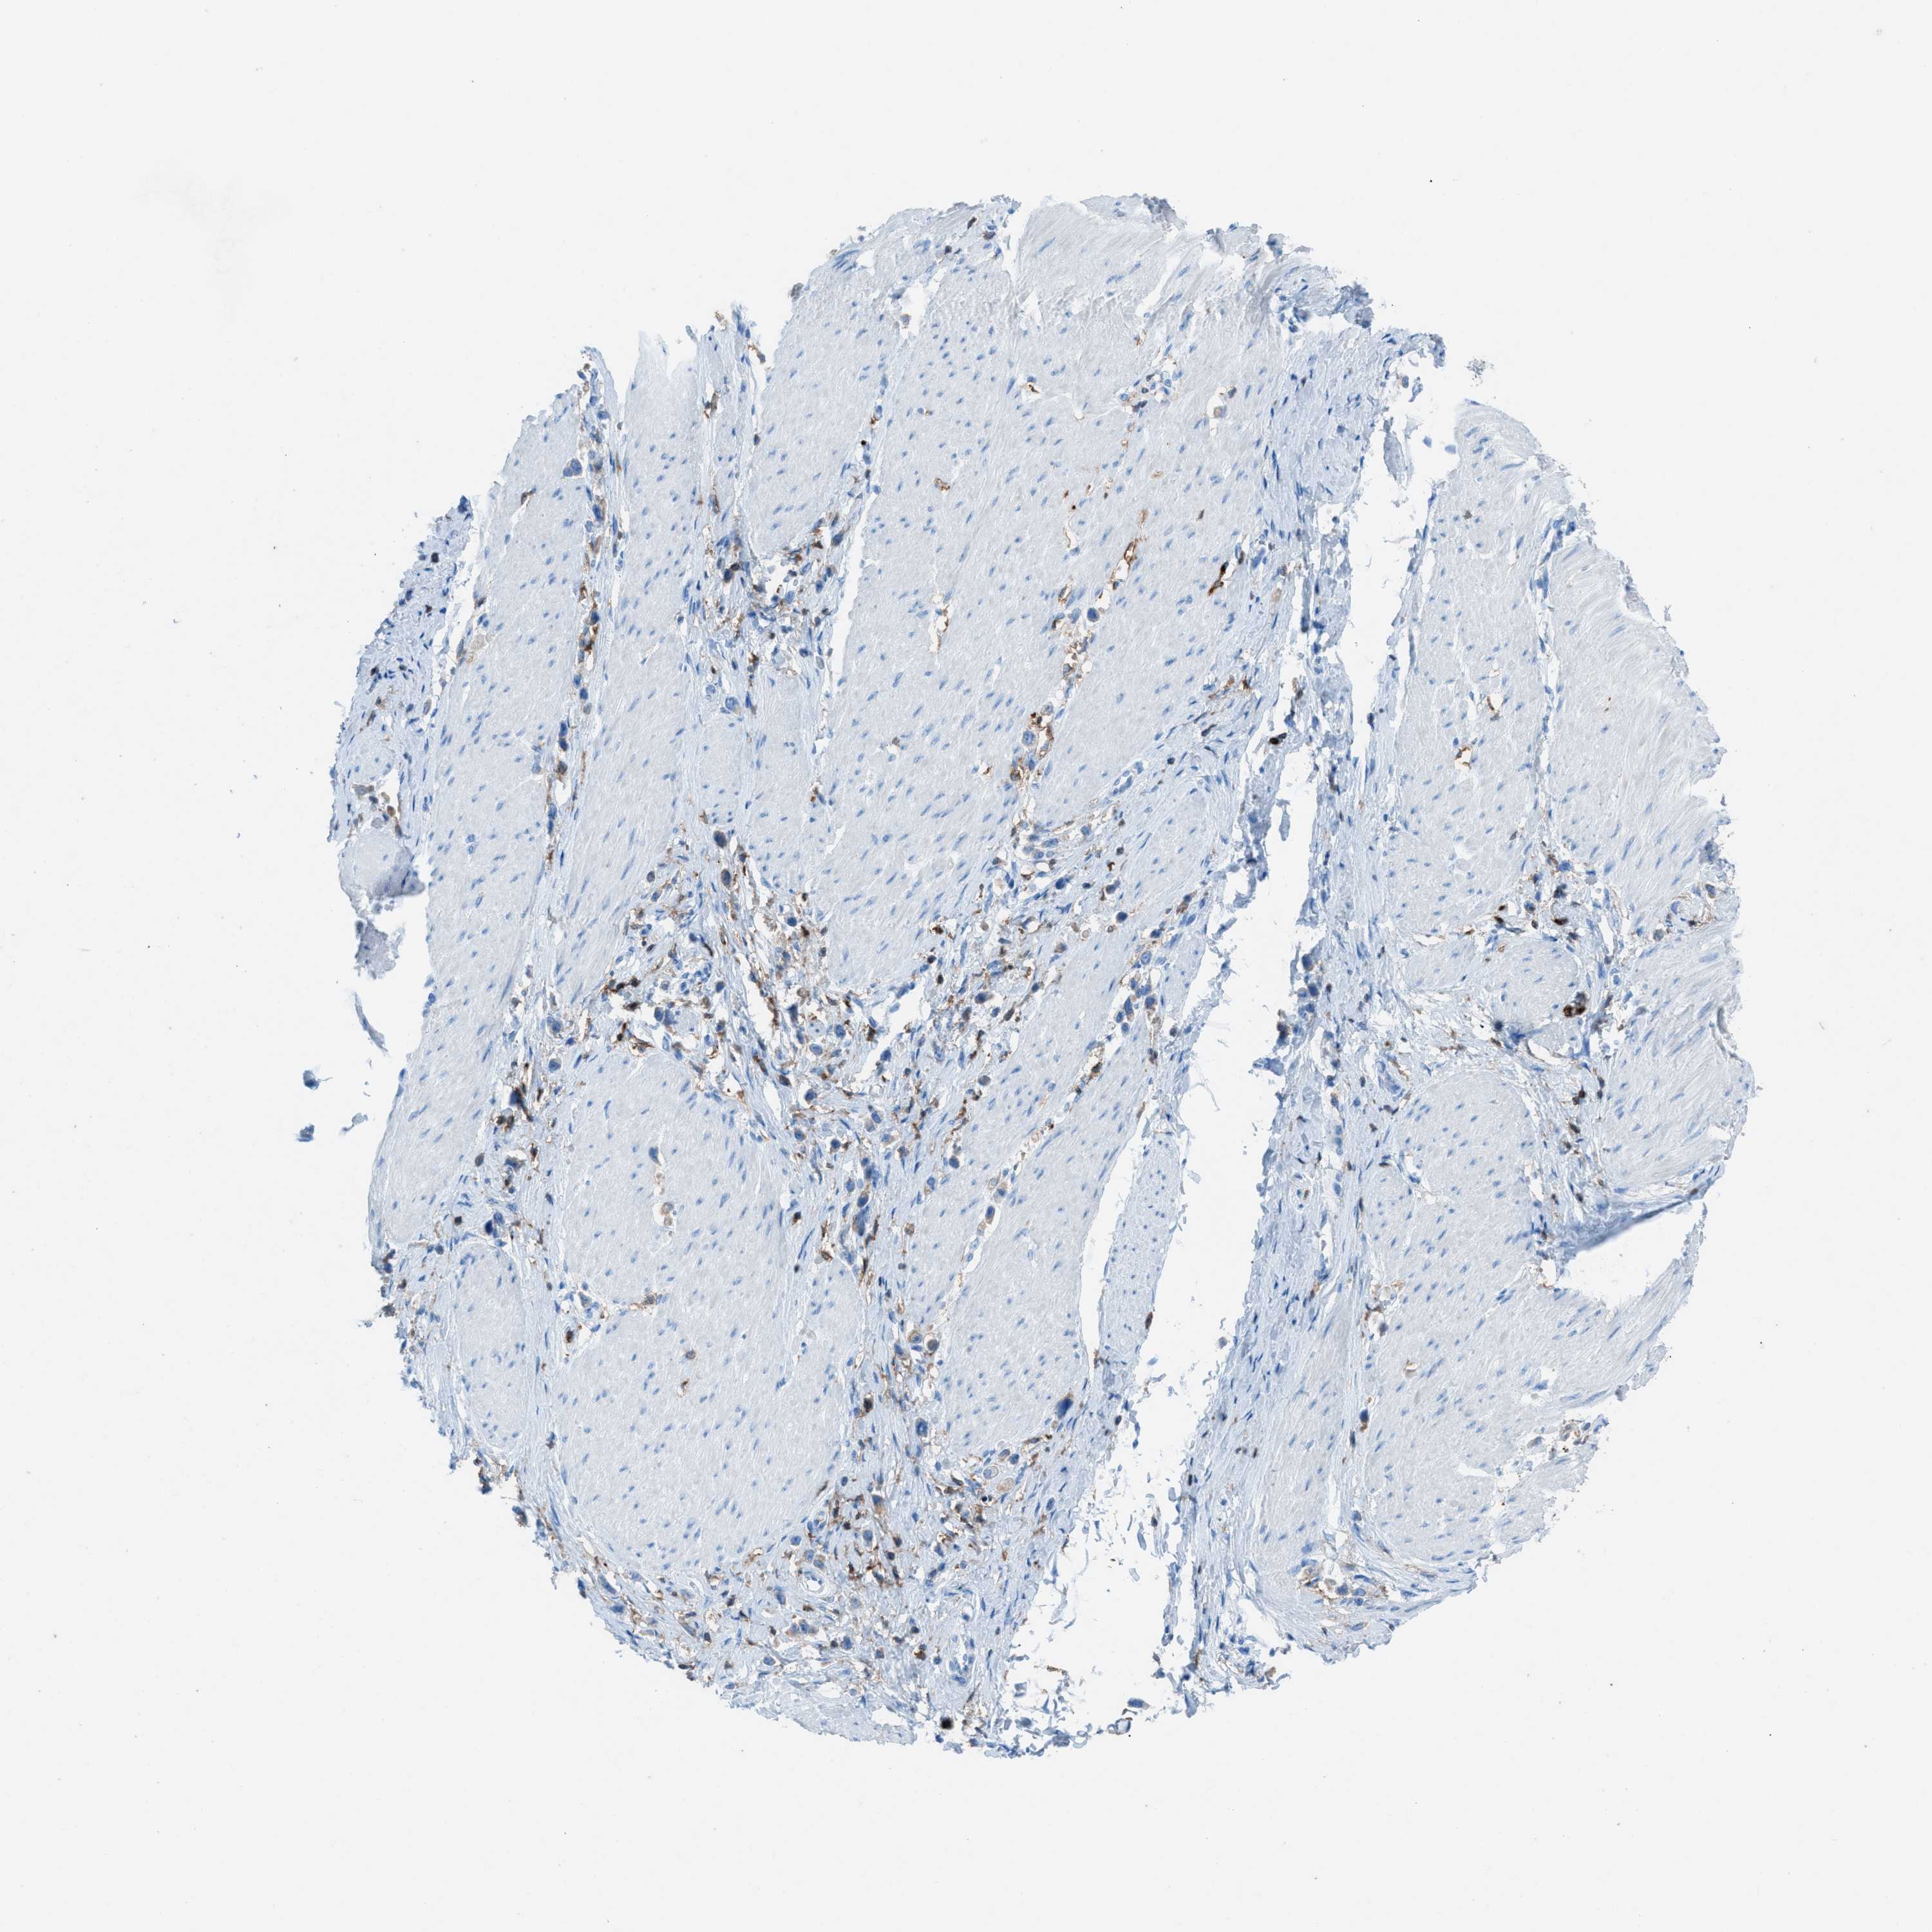

STOMACH CANCER - Protein expressioni

A mouse-over function shows sample information and annotation data. Click on an image to view it in a full screen mode. Samples can be filtered based on level of antibody staining by selecting one or several of the following categories: high, medium, low and not detected. The assay and annotation is described here.

Note that samples used for immunohistochemistry by the Human Protein Atlas do not correspond to samples in the TCGA dataset.

Antibody stainingi

Antibody staining in the annotated cell types in the current human tissue is reported as not detected, low, medium, or high, based on conventional immunohistochemistry profiling in selected tissues. This score is based on the combination of the staining intensity and fraction of stained cells.

Each image is clickable and will lead to virtual microscopy that enables deeper exploration of all samples and also displays staining intensity scores, fraction scores and subcellular localization as well as patient and tissue information for each sample.

Antibody HPA008877

Antibody HPA016894

Staining

High

Medium

Low

Not detected

Intensity

Strong

Moderate

Weak

Negative

Quantity

>75%

75%-25%

<25%

None

Location

Nuclear

Cytoplasmic/membranous

Cytoplasmic/membranous,nuclear

Adenocarcinoma, NOS